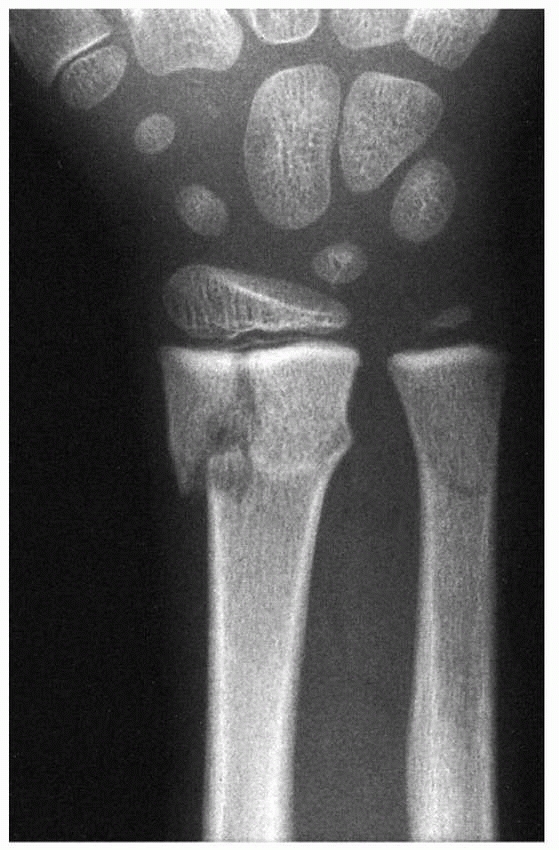

| Figure 5-44 Fat used as an interposition material in partial physeal arrest resection can persist and hypertrophy during longitudinal growth. A. Radiograph appearance after traumatic distal radial physeal arrest resection. B. Appearance 5 years later. Longitudinal growth between the metallic markers is obvious. The fat-filled cavity created at physeal arrest resection has persisted and elongated with distal radial growth. |